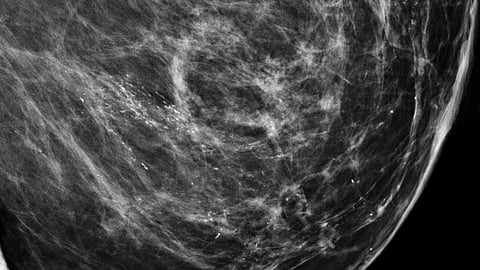

Using low-dose X-rays, mammograms can show abnormal areas or tissues in your breast and can help detect cancer before you have symptoms. Your breast is placed in a special machine between two plates. The plates move together to compress your breast tissue, so it’s easier for the X-ray to obtain a clear image. Once the images are created, they’re stored on a computer where they can be viewed and analyzed by the radiologist and your doctor.